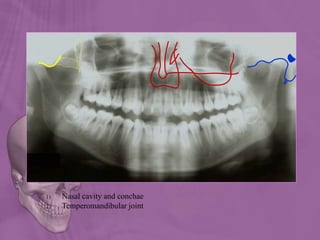

1) Nasal cavity and conchae

2) Temperomandibular joint